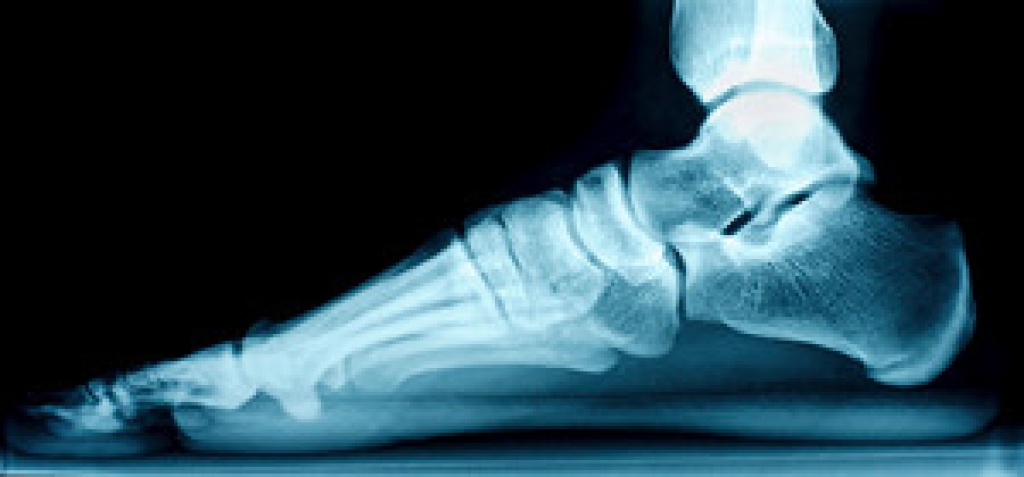

Cracked heels, if left untreated, can be an incredibly uncomfortable condition to deal with. If the cracks or fissures of the heel become deep enough, those affected may experience pain while standing, walking, or when putting any amount of pressure on the heels. Those who are obese, stand for long periods of time, or frequently wear open back shoes, may be more susceptible to developing cracked heels. Some of the first symptoms you may notice with this condition can include a hardening or thickening of the skin on the heels. In some cases, corns or calluses may form on the heel as well. In more severe cases, the heels may become discolored or begin bleeding, which is often indicative that an infection has formed. For more information, or to best treat cracked heels, it is suggested that you consult with a podiatrist for professional care.

Cracked heels appear unappealing and can make it harder for you walk around in sandals. Aside from looking unpleasant, cracked heels can also tear stockings, socks, and wear out your shoes. There are several methods to help restore a cracked heel and prevent further damage.